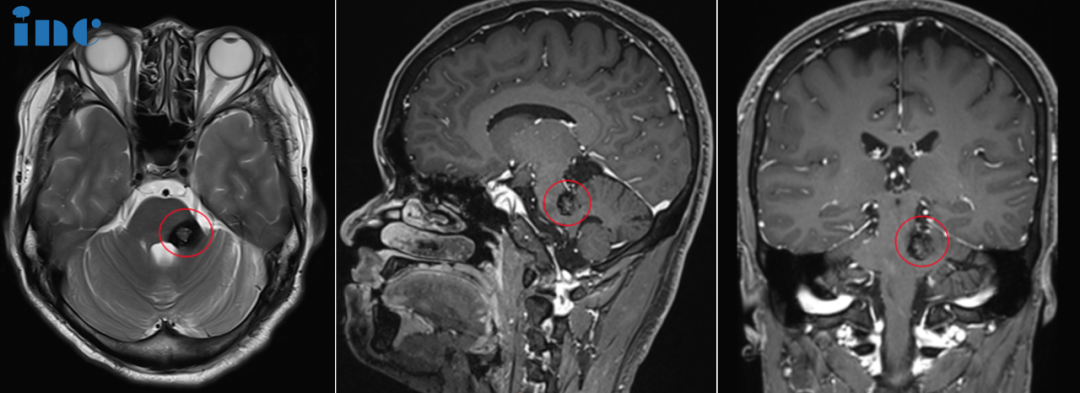

经历长达7年疾病折磨,三次脑干出血,甚至送入ICU抢救,但"就诊多家医院,各大医院教授均表示手术风险过高,建议保守治疗,不知如何抉择"。多次被建议保守观察,病情持续延误。巴教授明确回复,对于海绵状血管瘤不存在任何药物或放疗可有效治疗。手术切除是唯一治疗海绵状血管瘤的方法。影像学显示出血风险持续存在,应尽早手术消除再出血风险。